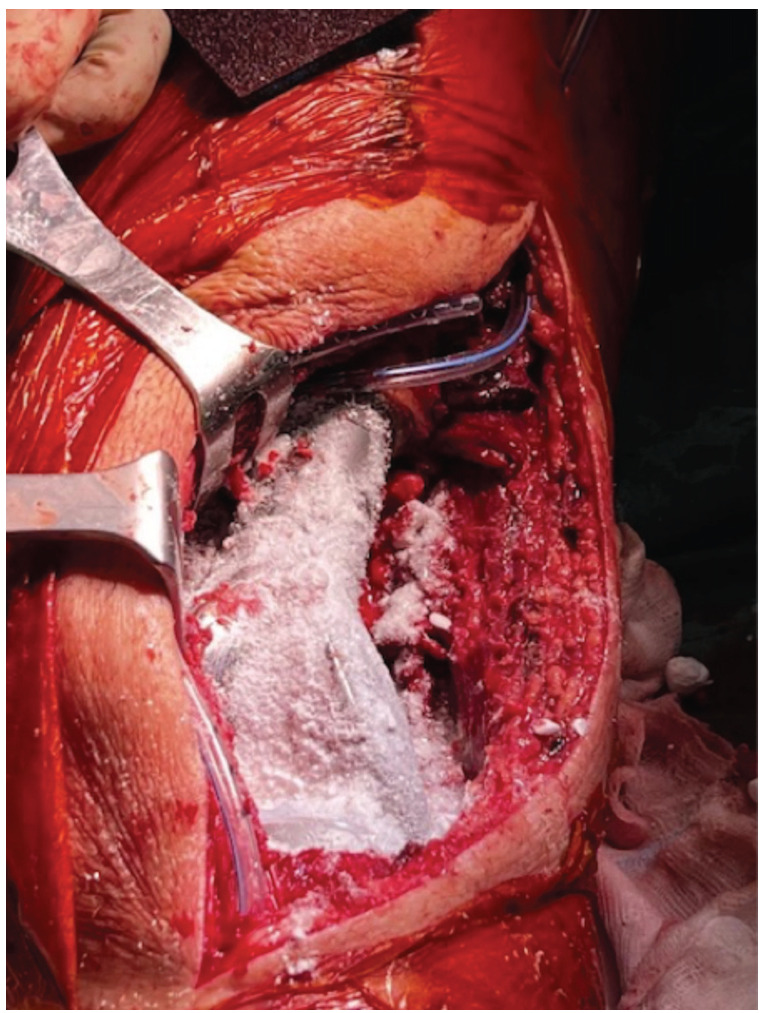

Materials and methods: Fifty oncological cases treated with massive bone resection and the implant of a megaprosthesis were included in our study. Among them, 22 [(GGroup A) received one gram of vancomycin powder on the surface of the implant and another gram on the surface of the muscular fascia]. The remaining 28 did not receive such a treatment (Group B). The rest of surgical procedures and the follow-up were the same for the two groups. Patients underwent periodical outpatient visits, radiographs and blood exams' evaluations. Diagnosis of PJIs and adverse reactions to topical vancomycin were recorded.

Results: None of the cases treated with topical vancomycin developed infections, whereas 6 of the 28 cases (21.4%) who did not receive the powder suffered from PJIs. These outcomes suggest that cases treated with VP had a significantly lower risk of post-operative PJI (p=0.028). None of our cases developed acute kidney failures or any other complication directly or indirectly attributable to the local administration of VP.

Conclusions: The topical use of vancomycin powder on megaprosthetic surfaces and the overlying fascias, alongside with a correct endovenous antibiotic prophylaxis, can represent a promising approach in order to minimise the risk of periprosthetic infections in orthopaedic oncology surgery.